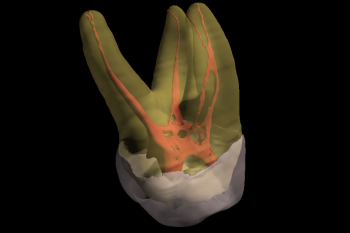

Conventional intra-oral radiography provides clinicians with cost-effective, high-resolution imaging that continues to be the front-line method for dental imaging. However, it is clear that there are many specific situations where the 3-D images produced by CBCT facilitates diagnosis and influences treatment. The usefulness of the CBCT cannot be disputed. It is a valuable task-specific imaging modality, producing minimal radiation exposure to the patient and providing maximal information to the clinician.

The introduction of the surgical operating microscope (SOM) to endodontitcs has dramatically changed the practice of the specialty. The microscope, within the last two decades has revolutionized the way procedures are performed. Each root canal therapy and examination is performed with the Zeiss OPMI Microscope. With the Zeiss OPMI Microscope, details and fine structures are clearly visible at high magnification levels. It enables the operator to better visualize the regions of interest and consistently provide patients with high-quality examinations and treatments.